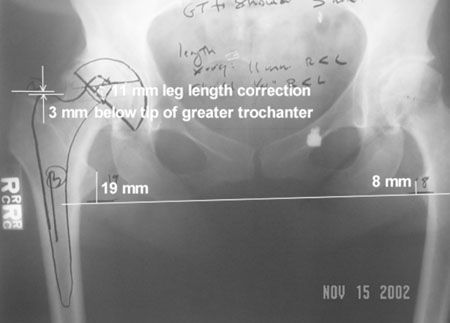

Actualité Intérêt dans la PTH d'une voie d'abord postérieur unique et courte avec la tige sans ciment SL-Plus , Todd V. Swanson Desert Orthopaedic Center, Las Vegas, Nevada, Etats-Unis N°141 - Février 2005 ● 17 min de lecture